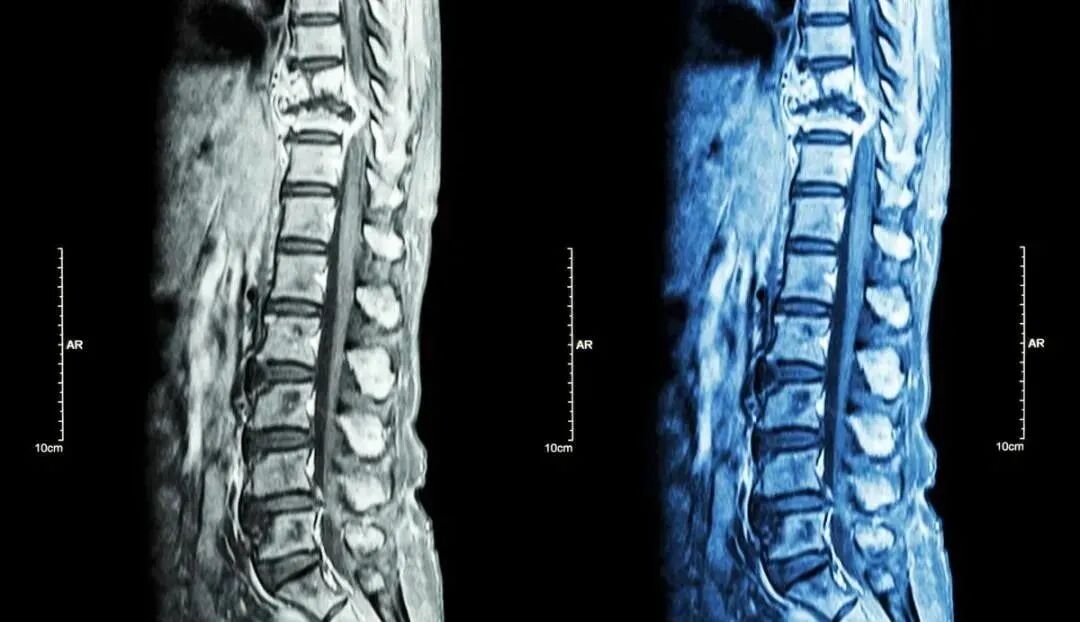

强直性脊柱炎(AS)是以侵犯脊柱且累及患者的骶髂关节以及周围关节组织的一种慢性进行性的炎症病变,以脊柱僵硬强直为特征,男性发病率明显高于女性,好发于男性青春发育期。

强直性脊柱炎是风湿免疫科的常见病。80%的强直性脊柱炎患者首先表现为下腰背部间歇性痛感,这种晨僵有时可以持续数小时之久。有些患者还伴有髋、膝、踝关节肿痛,臀部、腹股沟疼痛,颈背部钝痛,足跟痛、低热、乏力等。

强直性脊柱炎一般起病比较隐匿,早期可无任何临床症状,一旦发现就失去了最佳治疗时机,这时脊柱会连在一起,呈“竹节样”改变,像煮熟的虾一样弓起来,严重影响工作、生活甚至心理健康。人说,强直性脊柱炎是一种“不死的癌症”。据了解,因为传统疗法一般采用慢作用抗风湿药进行治疗,其疗效不显著并且复发率高、安全性差,对病情的缓解作用不明显,所以国内研究机构继而转向根据生物疗法研究出的干细胞疗法。